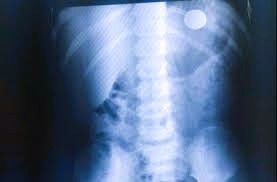

De acordo com as informações iniciais, a menina teria engolido quatro moedas de 5 e 10 centavos, o que levou familiares a acionarem a Unidade de Resgate por preocupação com possíveis complicações.

Ao chegar ao local, a equipe constatou que a criança já havia expelido as moedas antes do atendimento. Segundo o sargento Duarte, a menina estava tranquila, consciente e em estado estável no momento da avaliação.Ainda conforme o relato, a mãe demonstrava dúvidas se ainda havia algum objeto no organismo da criança. No entanto, foi verificado que as quatro moedas já haviam sido eliminadas, sem necessidade de encaminhamento emergencial naquele momento.Fonte: O Diário